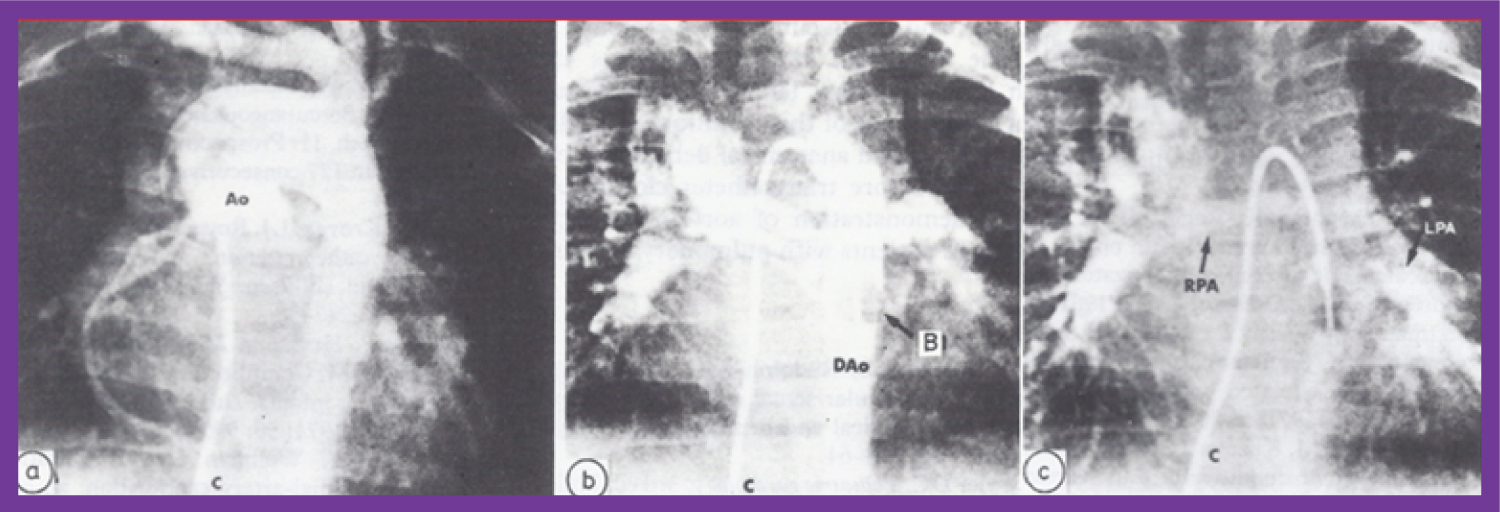

Figure 14: a) Selected frame of an aortic (Ao) root cineangiogram in postero-anterior view, three days after Waterston shunt surgery, demonstrating the prompt opacification of both branch pulmonary arteries via the Waterston shunt. The catheter (C) was positioned in the Ao via the umbilical artery; b) Selected frame of a left ventricular (LV) cineangiogram in postero-anterior view at the age of 12 months, demonstrating opacification of the aorta (Ao) with visualization of the right pulmonary artery (RPA) but without opacification of the left pulmonary artery (LPA). The catheter (c) is positioned in the LV via the patent foramen ovale and left atrium (not marked) [63]. View Figure 14

Figure 15: a) Selected frame of an aortic (Ao) root angiogram in postero-anterior view in an infant with tetralogy of Fallot with pulmonary atresia, with multiple aortopulmonary collateral arteries (MAPCAs); the right heart catheter (C) was advanced into the ascending Ao via the VSD. Note that multiple collateral vessels were seen, but there is no clear demonstration of these vessels; b) The same infant's cineangiogram, also in postero-anterior view, obtained by balloon (B) occlusion descending aortography, demonstrates several collateral vessels more clearly than can be seen in a. c) A delayed phase of b demonstrates the right (RPA) and left (LPA) pulmonary arteries. Dao: descending aorta [69]. View Figure 15